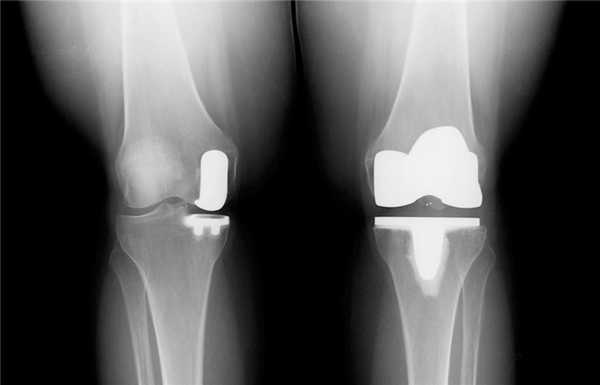

Одномыщелковая замена сустава на рентгене.

Сравнение двух типов операций.

Одномыщелковое протезирование подразумевает срок службы небиологического устройства максимум 7 лет. Тотальное замещение предусматривает время службы вживленного механизма от 15 лет. Ревизионное переносится сложнее, а риск инфекции и других негативных явлений почти в 2 раза выше, чем после первичной операции.